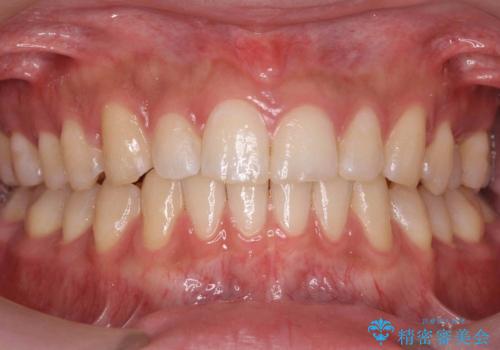

[ 引っ込んだ前歯を治したい ] 歯を抜かないマウスピース矯正

![[ 引っ込んだ前歯を治したい ] 歯を抜かないマウスピース矯正の症例 治療前](https://seimitsushinbi.jp/wp/wp-content/uploads/2024/03/IMG_1089-500x350.jpg?v=1711680738)

![[ 引っ込んだ前歯を治したい ] 歯を抜かないマウスピース矯正の症例 治療後](https://seimitsushinbi.jp/wp/wp-content/uploads/2024/03/5329ad9ea362646e5d4ee5f7b30cf319-500x350.jpg?v=1711680954)